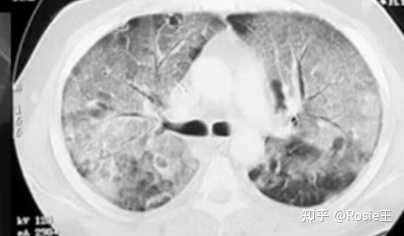

不知大家有没有发现,即便是新冠转阴之后,身体仍然会有其他不适,比如说咳嗽,想必大多数人都会有咳嗽不止的情况,包括最近新闻一直报道的白肺问题,是不是和咳嗽有关,WB上CY郝希纯医生 有总结到,我就简单搬运几点,所谓白肺指的是肺泡组织在X光或者是CT上表现为白色,

因此,A型流感感染大量细胞,导致病毒快速复制、广泛损伤、强大的抗病毒反应,并导致感染的上皮细胞死亡,而SARS-CoV-2感染可能导致空间局部感染。这可以解释COVID-19症状最小的患者在胸部CT上观察到磨玻璃浸润的局限性。研究者推测携带SARS-CoV-2的肺泡巨噬细胞可能在肺泡间传播病毒。在每一个新的感染区域,含有病毒的肺泡巨噬细胞和激活的T细胞之间的正反馈循环可以促进持续的损伤和炎症。

第一方面,因为感染新冠后,身体很多部位都有可能被攻击,或出现损伤,产生炎症反应。当感染十多天以后,机体的抗病毒能力较强,游离的病毒或是被感染的细胞基本被消灭干净。但人体重要器官或组织仍需要较长时间修复,个别组织细胞在即使没有病毒情况下也会出现长时间的炎症反应,具体病理性机制可参考图片。所以机体完全恢复时间和病毒清除时间并不对等。